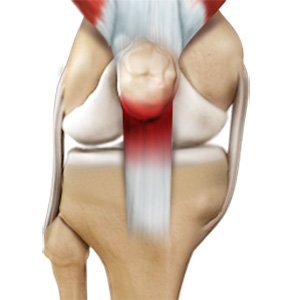

Patellar Tendon Rupture

The patellar tendon works together with the quadriceps muscle and the quadriceps tendon to allow your knee to straighten out. Patella tendon rupture is the rupture of the tendon that connects the patella (kneecap) to the top portion of the tibia (shinbone).